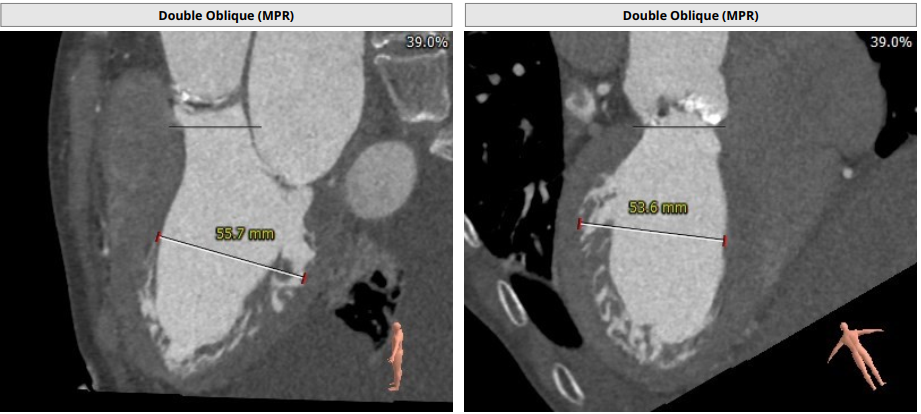

Tepy1型二叶瓣,中度钙化,瓣环直径25.6mm,LVOT32.5mm,窦部短轴最窄处22.8mm,综合考虑DOWNSIZE选择L26或者L29瓣膜。冠脉高度尚可,STJ较高,以及二叶瓣均可降低冠脉风险,整体评估冠脉风险较小,决定术中使用22mm球囊预扩确认冠脉风险及瓣膜选择。

入路情况较为特殊,右股入路扭曲,左股尚可,腹主迂曲,上大鞘和过输送器时应轻柔,以防止血管并发症。决定左股作为主入路,左桡作为辅路。弓部呈锐角,过弓时应注意血管损伤,必要时借助抓捕器。